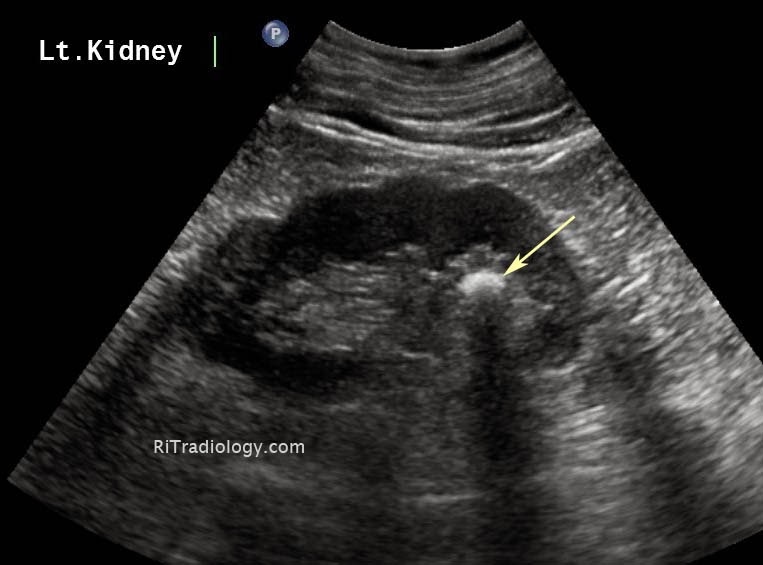

Sonography of the left kidney. A hyperechoic mass measuring 8 mm in What Does Shadows On Kidneys Mean it is true that a ct will pick up a tumour, but it may also show a shadow if there has been infection present for a while (this may be low. The possible significance of light/dark spots in a scan of. main symptoms of kidney cancer. Early kidney cancers often don’t cause any signs or symptoms, but larger. What Does Shadows On Kidneys Mean.